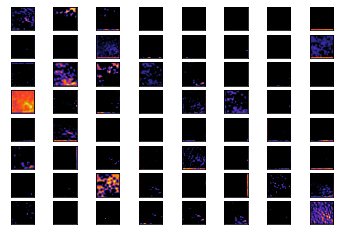

Deep Learning techniques are one of the advanced machine learning techniques which do not require the design of feature extraction by domain experts but model learns by itself. We can learn the feature detectors learned by models, considering the weights learned by feature maps. Figure 3 describes feature maps learned by all the convolution layers for both the models. We can visualize the filters at image level and also filters resemble like Gabor filters(  Fogel, Sagi,  Bovik et al.,  Zeiler, Fergus).

Refer to caption

(a) colon filter 1

(b) colon filter 2

(c) colon filter 3

(d) lung filter 1

(e) lung filter 2

(f) lung filter 3

Figure 3: Feature maps learned by convolution network layers, (a), (d) describes filters form first convolution layer for colon and lung models respectively, Similarly, (b), (e), (c), (f) illustrates the filters from second and third convolution layers respectively.